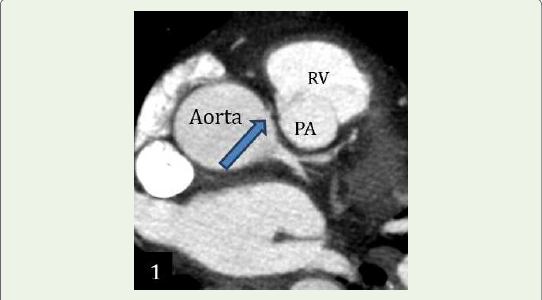

Case 1: A 70-year-old female with c/o dyspnea on exertion, case

of hypertension and diabetes mellitus, demonstrated an anomalous

origin of Right coronary artery from le coronary sinus, RCA seen

passing between the pulmonary trunk & ascending aorta– Malignant

inter-arterial course of RCA.Case 2: A 36-year-old male smoker with c/o chest pain & positive stress test and without any comorbidities, demonstrated an anomalous origin of Le main coronary artery from non-coronary cusp with retro-aortic course.

Figure 1:Case 1: Maximum intensity projection reconstruction shows

anomalous origin of right coronary artery from left coronary sinus, RCA seen

passing between the pulmonary trunk & ascending aorta– Malignant interarterial

course of RCA. Note the narrow caliber and acute angulation of RCA.